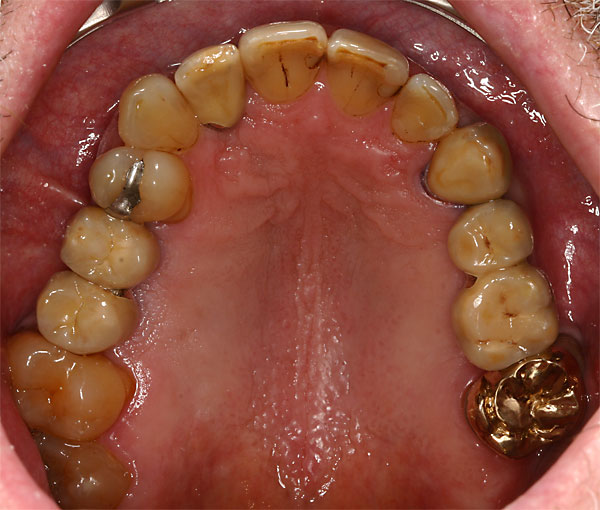

FOTO festsitzende Brücken im Mund |

Fall: festsitzender Zahnersatz im Oberkiefer auf 8 Implantaten